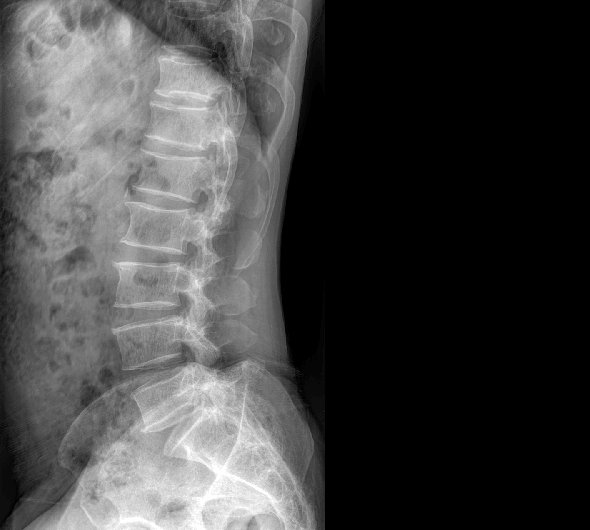

臨床圖像